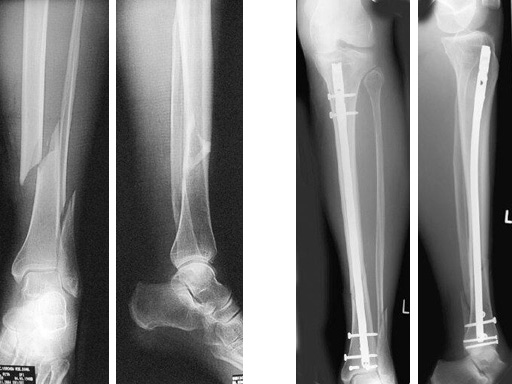

64-year-old woman with an open distal tibial fracture extending into the pilon treated with ETNS.